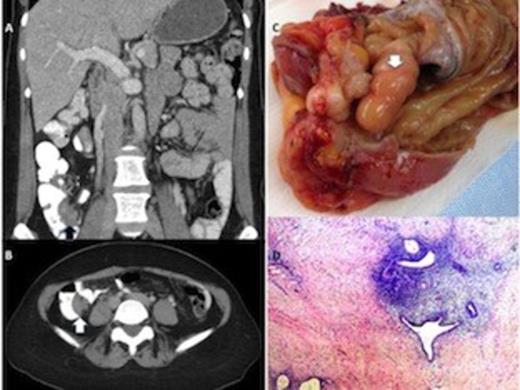

We felt that her symptoms were not consistent with biliary dyskinesia, so we ordered a computed tomography (CT) scan to delineate the cause of her pain (Figure A, B). The CT scan revealed an apparent mass causing a filling defect of the cecum near the appendiceal orifice. A subsequent colonoscopy showed that the appendix was partially intussuscepted, with mucosal thickening at the appendiceal orifice. Because a mucinous cystadenoma or cystadenocarcinoma was a possibility, we deferred a biopsy.

The patient underwent a laparoscopic ileocecectomy and a cholecystectomy with intraoperative cholangiography. During the operation, we noted a firm mass at the cecum; in addition, the appendix was partially intussuscepted (Figure C). The specimen was sent for frozen-section analysis, which pointed to a presumptive diagnosis of endometriosis.

The final histopathologic review of the mass was diagnostic of transmural appendiceal endometriosis (Figure D). The patient recovered uneventfully and was discharged home. She has since been seen in our clinic and is free of symptoms. She was referred to our gynecology colleagues for management of her endometriosis.